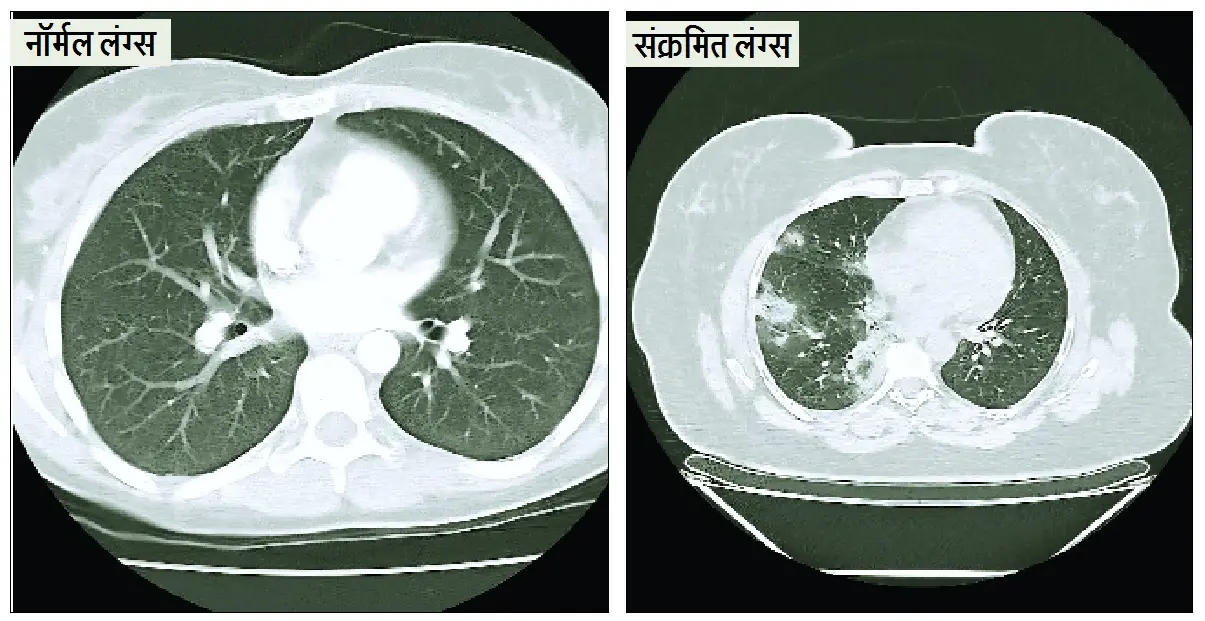

बिगड़े मौसम ने बिगाड़ी सेहत : एडिनोवायरस-इन्फ्लुएंजा की दोहरी मार, निमोनिया और ब्रोंकाइटिस के मरीज बढ़े

बदलता मौसम बीमारियों का घर बन गया है! एडिनोवायरस और इन्फ्लूएंजा के बढ़ते मामलों के साथ निमोनिया और ब्रोंकाइटिस के मरीजों की संख्या में भारी वृद्धि हुई है, जानिए कैसे करें बचाव और क्या हैं लक्षण।